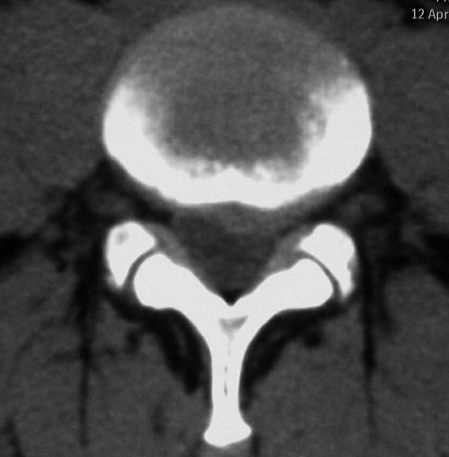

CT显示L4/5节段的椎间盘突出脱垂型(图1)。MRI示L4/5节段的椎间盘突出到Ⅲ层面(图2)。红外热成像显示左侧下肢的皮温明显低于右侧(图3)。

图1 CT轴位片L4~5节段的椎间盘突出:脱垂型